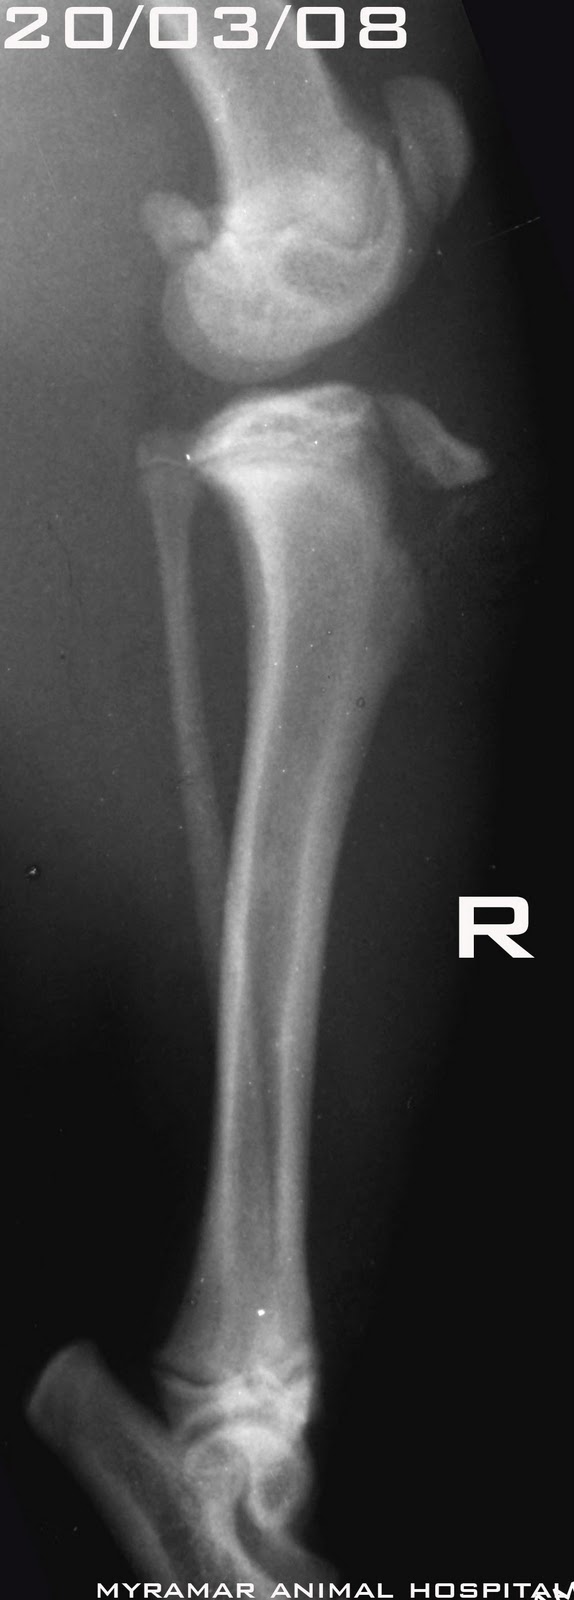

Llega Rosie, Chihuhua de 3 años, presentando cojera de extremidad posterior derecha debido a posible luxación medial rotuliana.

Tras estudio radiológico se confirma la lesión: Luxación medial rotuliana grado 3.

Se presentan radiografías pre y posquirúrgicas y algunas fotos intraoperatorias.